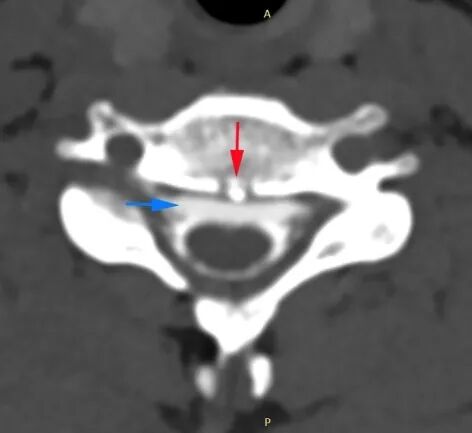

江女士的脊柱磁共振检查 可见第1、2胸椎之间有“骨刺”形成(红箭头) 刺破硬脊髓膜,造成脑脊液外漏(蓝箭头) 站立时头痛,躺下头不痛 警惕低颅压 浙江大学医学院附属邵逸夫医院神经内科副主任王谨主任医师解释: 自发性颅内低压是由于脊髓脑脊液渗漏,导致脑脊液容量减少所产生的。 我们的脑子和脊髓腔是一个密闭的囊腔,脑脊液充满在囊腔中起到了托浮作用,避免脑神经受到震荡。 一旦脊髓部位的囊腔(硬脊膜)发生破口,导致脑脊液渗漏、容量减少,就会导致低颅压。 低颅压最常见的表现是:站立时头痛,躺下头痛缓解。但部分患者可发生颅内出血、脑子下沉等严重并发症,威胁生命。